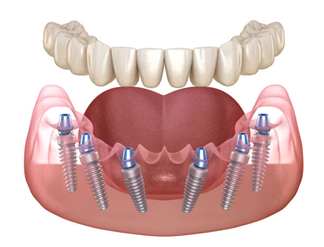

All-on-6 Dental Implants

Similar to All-on-4 but with six implants per arch for additional support and load distribution. This option is recommended when higher strength or a broader prosthetic base is required, especially in the upper jaw.